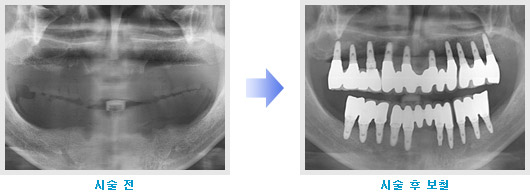

무치악임플란트

잇몸에 치아가 하나도 없는 것을 무치악이라고 합니다.

자연 치아는 위 아래 14개씩 모두 28개입니다.

자연 치아가 충치, 잇몸 질환, 사고 등의 이유로 모두 상실된 경우에 원래 자연 치아처럼 모두 재현해 드릴 수 있는 임플란트 시술 방법입니다.

치료사례